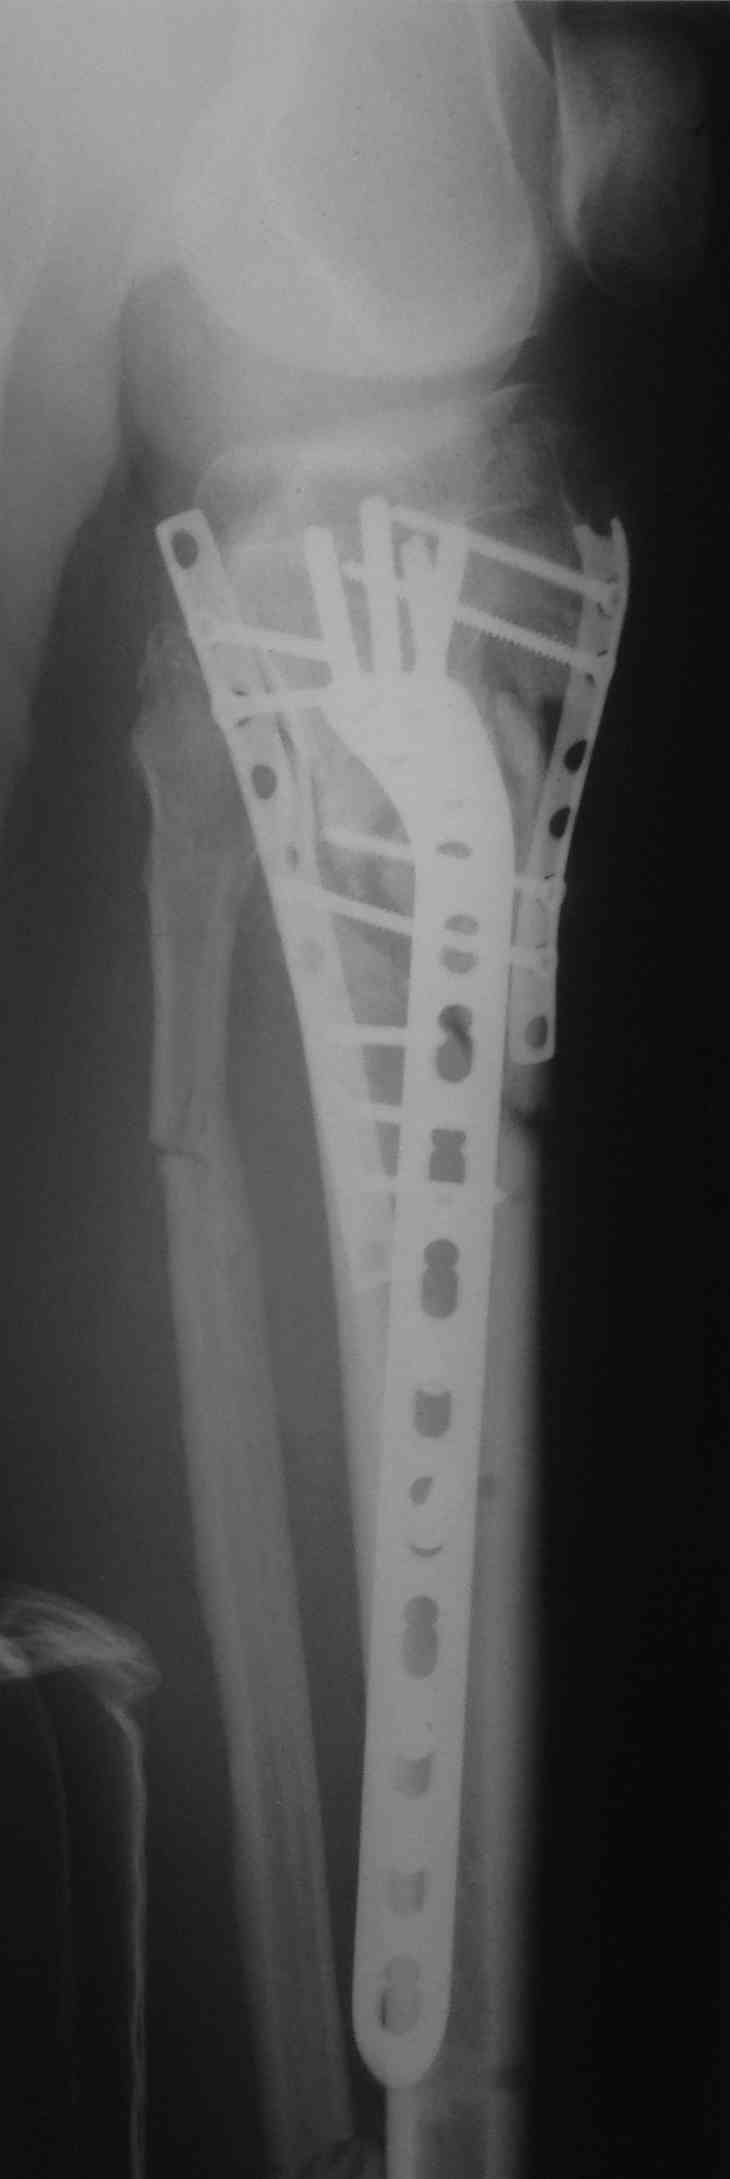

перелом мыщелков голени и вывих бедра (результат операции)

продолжение темы http://weborto.net/forum/1435828753

Кожа пришла в норму только к полутора месяцам, операция из двух доступов.